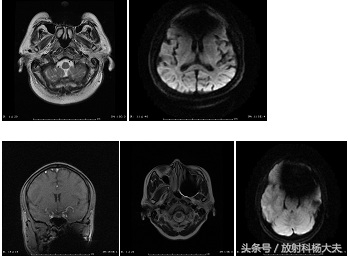

正常颅脑扫描图像

有假牙头部做磁共振有影响吗,有假牙能做核磁共振全过程视频

伪影较轻的假牙图像

伪影较重的假牙图像

上文中可以发现,在伪影较重的图像中,DWI图像受到了严重的影响,不利于疾病的诊断与鉴别诊断。